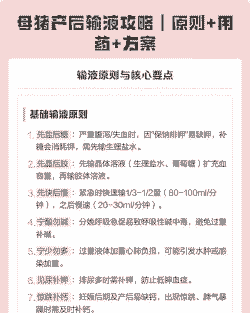

母猪产后消炎输液配方有多种,以下提供几种常见的配方:

配方一

第一瓶:氯化钠生理盐水500毫升 + 青霉素3支 + 鱼腥草3-4支

第二瓶:葡萄糖水500毫升 + 维生素C(VC)10毫升

如果体温低,可以添加葡萄糖酸钙50-100毫升

输液时间一般选择分娩7-8头后进行,使用绑定绳绑定母猪进行输液

配方二

0.9%生理盐水250毫升 + 阿莫西林

10%葡萄糖500毫升 + 复合维生素B

甲硝唑8-10瓶

配方三

普鲁卡因青霉素400万单位 + 庆大霉素40万单位 + 鱼腥草20mL + 缩宫素20至30万单位混合注射

每天一次,连用3至5天

配方四

阿莫西林(或头孢类)+ 恩诺沙星(或氧氟沙星)+ 鱼腥草 + 缩宫素

配方五

500mL生理盐水 + 30mL黄芪多糖注射液 + 4g阿莫西林粉 + 半支缩宫素

500mL 10%葡萄糖溶液 + 20mL复合维B注射液 + 30mL 10%林可霉素注射液 + 半支缩宫素 + 地塞米松10mg

连用两至三次,直至母猪精神食欲正常

配方六

头孢噻呋混悬液 + 益母生化散 + 林可大观霉素

产后当天和产后第三天分别肌注一次头孢噻呋混悬液

产后14天内饲料中按照2kg/吨添加益母生化散和400g/吨添加林可大观霉素

这些配方主要根据抗菌谱、药效持续时间以及猪场的具体情况来选择。建议在实际应用中,根据母猪的具体情况和兽医的建议进行调整,并确保药物使用的安全性和有效性。